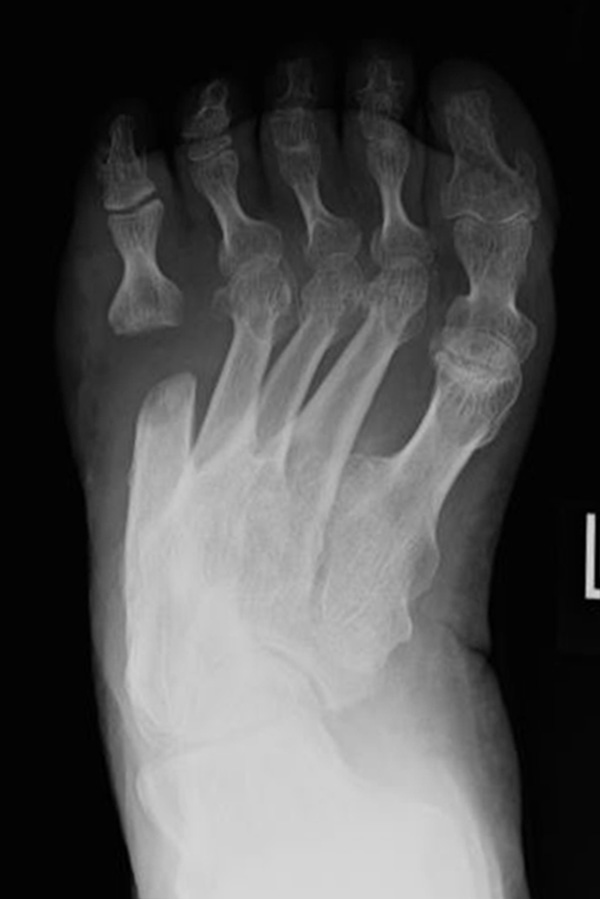

Abb. 12a: Typ III Deformität präoperativ im belasteten dp Röntgenbild.

Abb. 12b: Dorsoplantare Röntgenkontrolle nach medial schließender Osteotomie mit Schraubenosteosynthese.

Abb. 12c: Schrägaufnahme nach medial schließender Osteotomie mit Schraubenosteosynthese.

Abb. 12d: Seitliche Aufnahme nach medial schließender Osteotomie mit Schraubenosteosynthese.